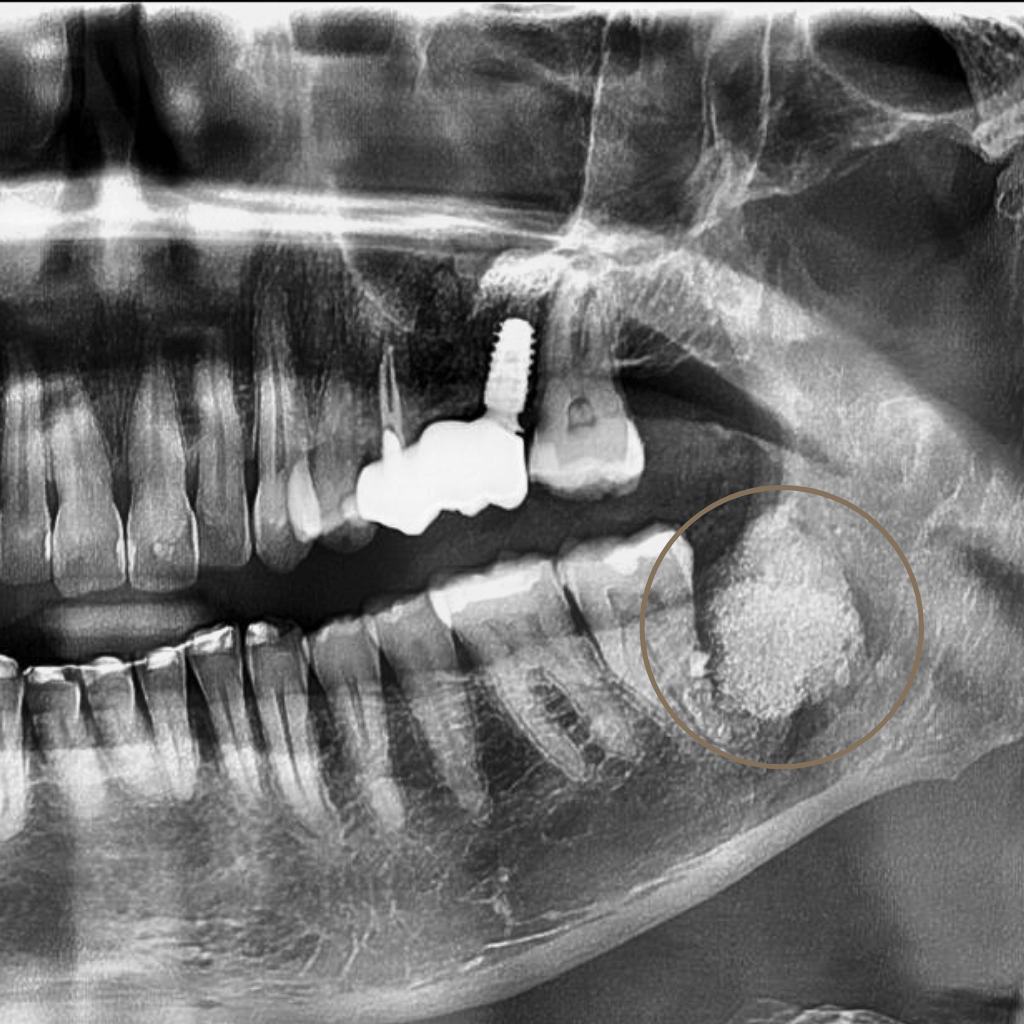

Екстракцията е хирургична процедура, при която зъбът се отстранява, когато неговото запазване не е възможно или би компрометирало цялостното орално здраве. В Aesthetico екстракциите се извършват след внимателна оценка и с ясна цел – лечение, облекчаване на болката и създаване на стабилна основа за последващи стъпки.